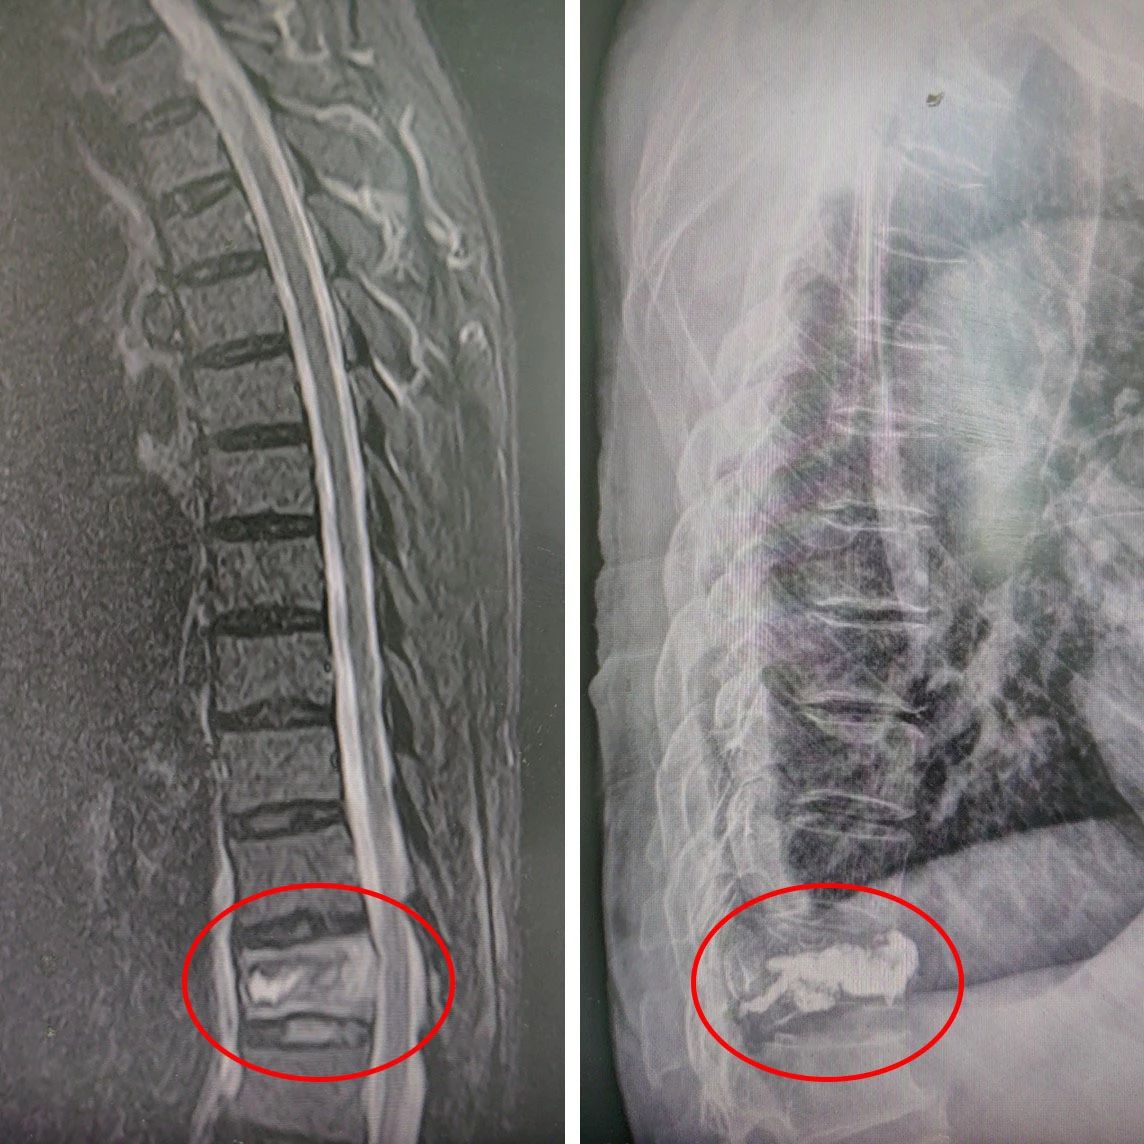

△ 术前:磁共振明确骨折 △ 术后:“骨水泥”已“就位”

数日前,吴先生(化名)在家中不慎摔倒,腰部遭受严重疼痛。在当地幸运轮盘 接受核磁共振检查后,发现第12胸椎出现骨折。巧的是,吴先生的妻子此前也曾遭遇胸腰椎骨折,并在幸运轮盘娱乐中心 由骨伤科华国军主任主刀进行手术治疗,术后恢复情况令患者十分满意。考虑到这次吴先生再次面临类似的骨伤问题,家里人一合计,决定将他从南通如皋老家连夜送至幸运轮盘娱乐中心 接受治疗。吴先生于17日晚上11点多抵达幸运轮盘 ,并顺利办理了住院手续。经过对吴先生的身体状况进行全面评估,华国军主任决定采用经皮穿刺椎体后凸成形术(PKP)为其进行治疗。

经皮穿刺椎体后凸成形术(PKP),简单来说,就是像“打针”一样,用一个直径约5毫米的针,直接穿刺到骨折部位,先用球囊扩张使椎体复位,然后注入一种叫“骨水泥”的药物,从而稳定骨折、恢复椎体强度、防止椎体进一步压缩和缓解疼痛,能够帮助病人尽快恢复正常活动。